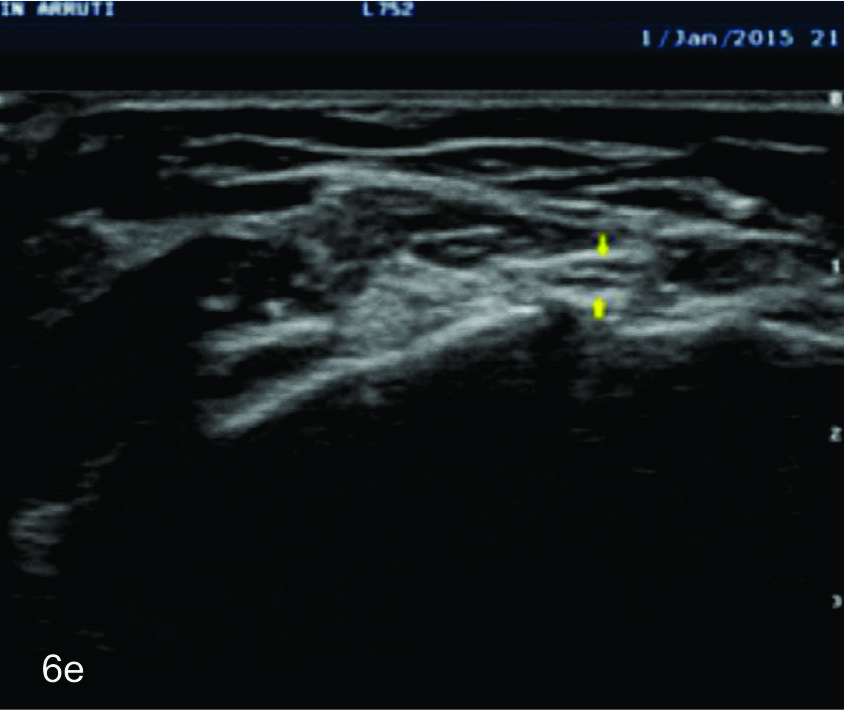

Figura 14 e, f, g y h

Lesión traumática del plexo braquial luego de accidente en moto.

EyF-Cortes comparativos a nivel de cara anterior de brazo derecho o afectado (E) y brazo izquierdo o sano (F), en donde se identifica la clara asimetría en el volumen y ecogenicidad de los planos musculares (flechas azules) en relación a cambios por atrofia. H- diáfisis humeral. GyH- Cortes comparativos a nivel de la cara anterior del antebrazo derecho o afectado (H) e izquierdo o sano (G), demuestra hallazgos similares. R- Diafisis radio, C- Diafisis cubito.